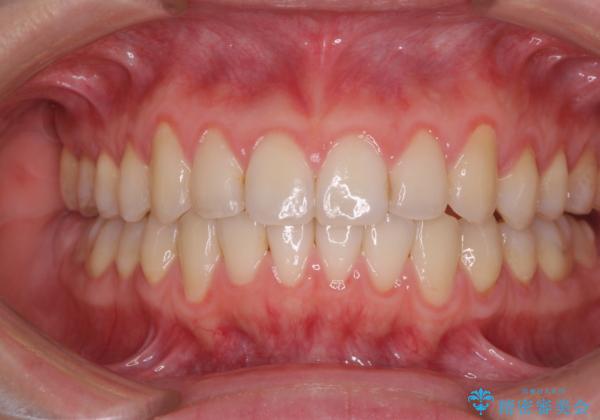

前歯のデコボコを治したい インビザラインによる矯正治療

- 上下前歯のデコボコを気にして来院された患者様です。

インビザラインによる上下歯列の側方拡大と後方移動、IPR(歯と歯の間を削る)にるスペースの獲得により歯列を整えることとしました。

1日22時間の装着時間をしっかり守ってくださったので、予定していた1年よりも早く治療を終えることができました。

インビザライン矯正特有の奥歯がしっかりと咬合しない感覚も改善され、大変満足していただきました。